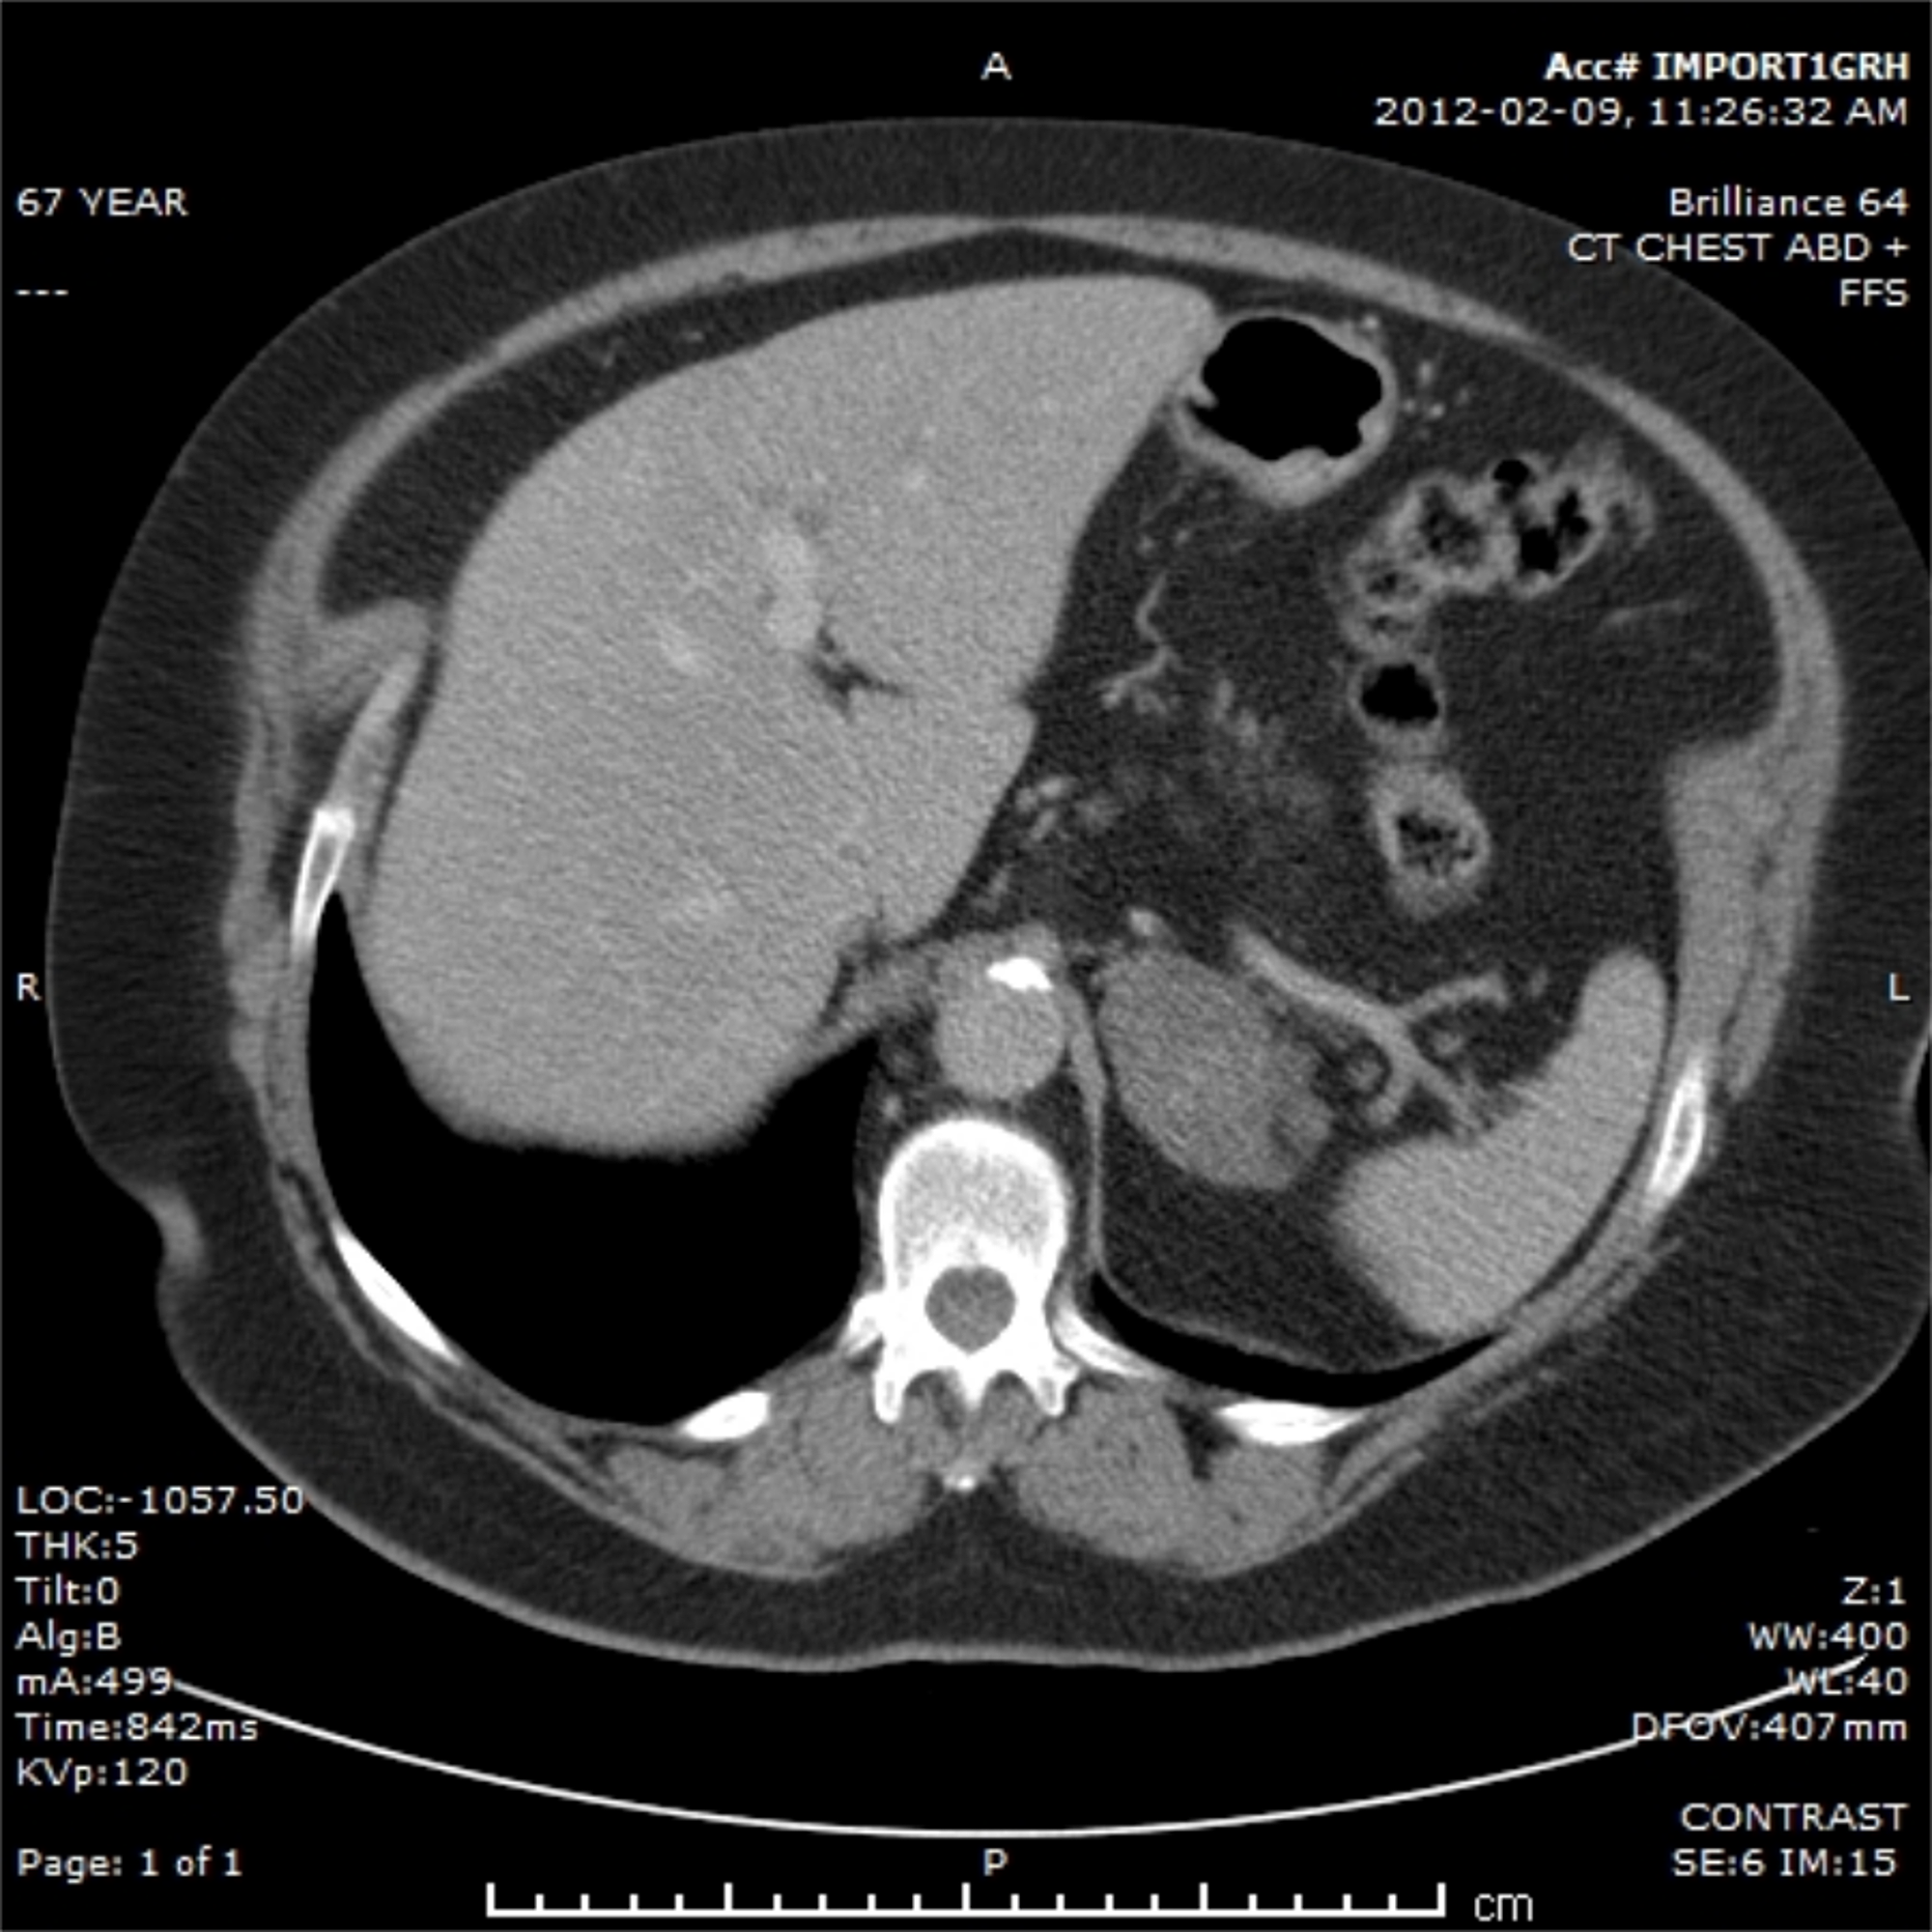

A 67-year-old female sought medical attention for an initially suspected diagnosis of pneumonia in January 2012. A chest X-ray was performed and revealed a suspicious mass in the right upper lobe of the lung. A computed tomography (CT) scan of the abdomen and chest demonstrated a 3.1-cm lesion in the right upper lobe with no hilar or mediastinal lymphadenopathy and a suspicious left adrenal mass, measuring 5.2 cm (Figure 1).